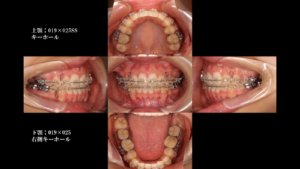

今回の症例では、親知らず(8番)の形や根の状態が非常に良かったため、「7番を6番の位置へ、8番を7番の位置へ」と移動させました。ここはかなり複雑ですが、歯の背番号を交代させていった感じです。

これにより、インプラントなどの人工物に頼ることなく、すべてご自身の天然歯で噛み合わせを完成させることができました。

下にこれまでの経過を載せています。 歯科セミナーでのケースプレゼンテーションで使用したものをそのまま載せます。